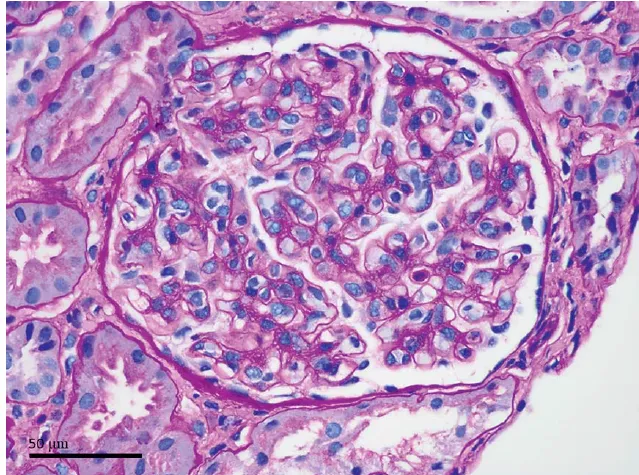

Uma causa incomum de hematúria glomerular intermitente!

Uma causa incomum de hematúria glomerular intermitente!